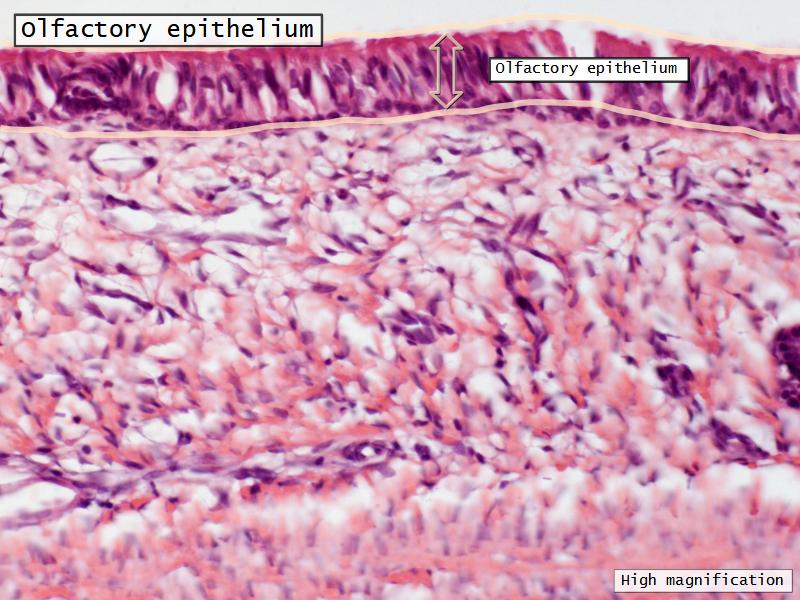

- Slide 108: Olfactory epithelium

Olfactory epithelium